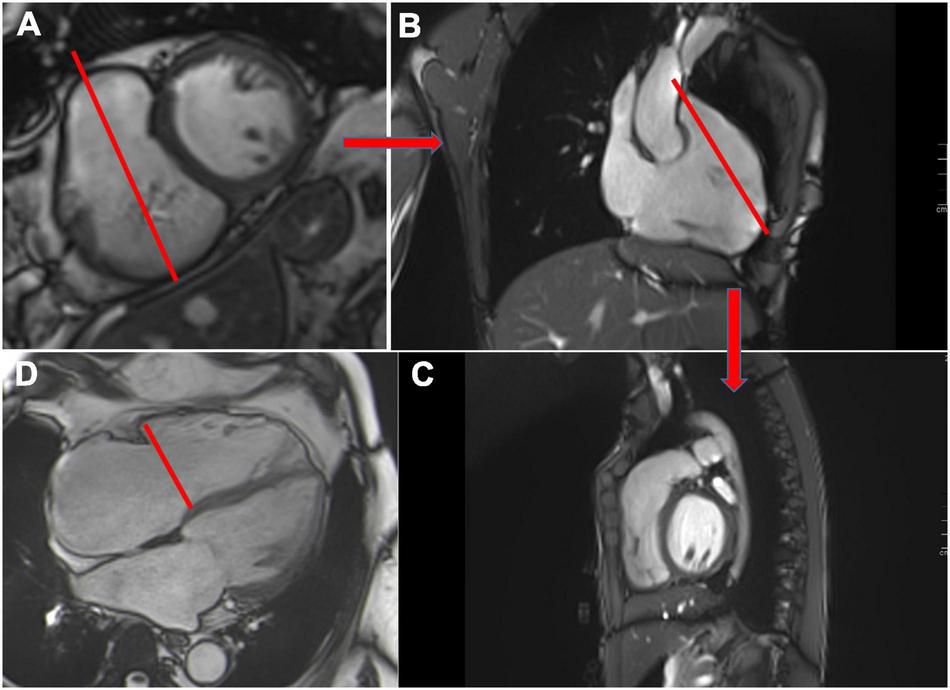

FIGURE 6

Cardiovascular magnetic resonance planes used for evaluation of the right ventricle. Short axis view (A), 3-chamber view (B) and RVOT (C). Example of tricuspid annular measurement in the 4-chamber view (red line) (D).